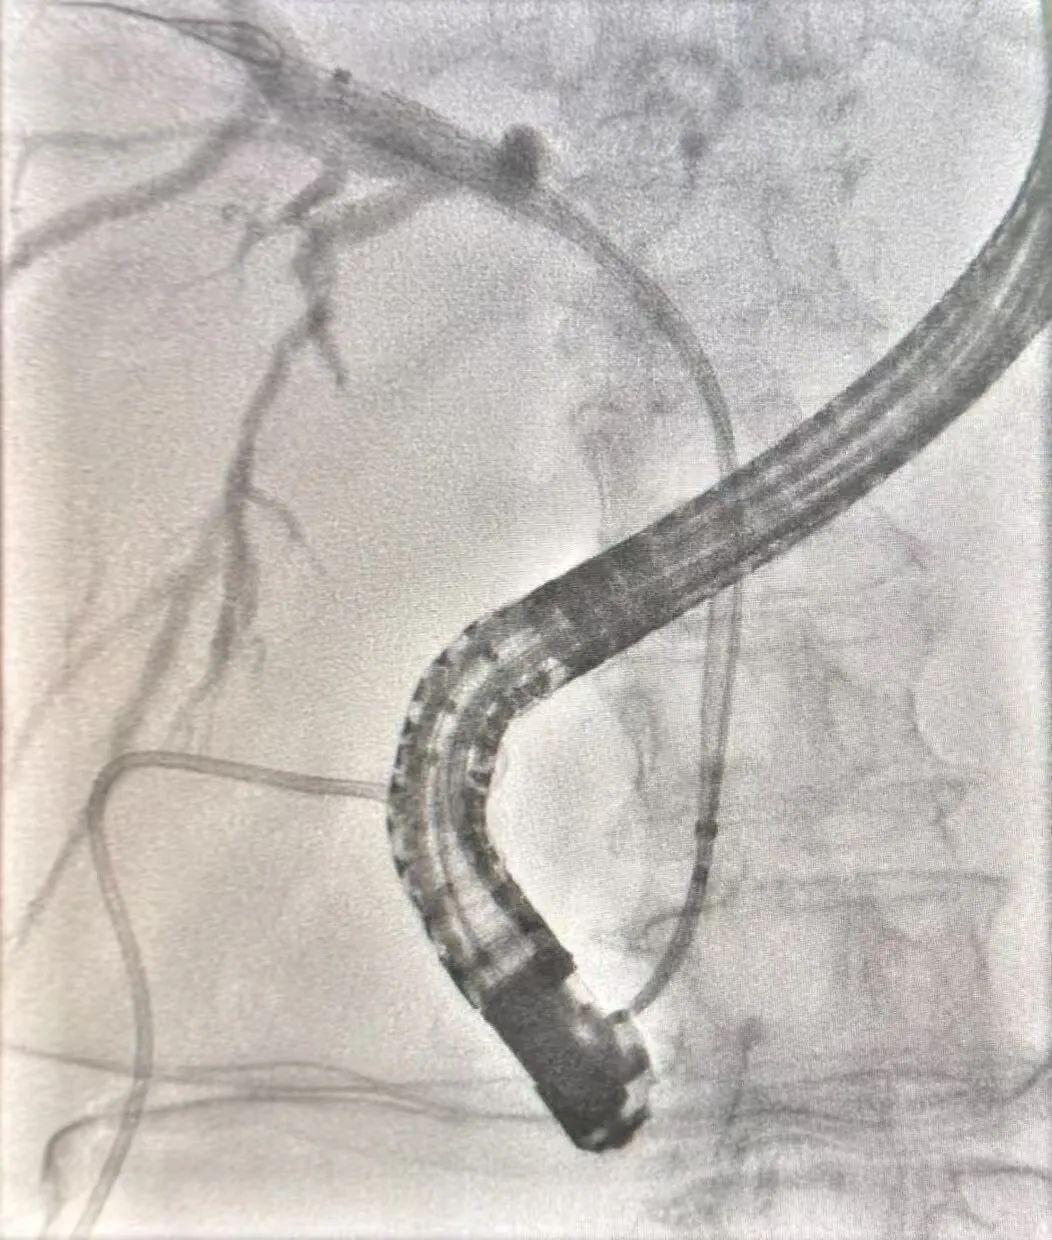

据悉,两位患者因胆总管狭窄收入消化内科,其中62岁的张先生系胰腺癌伴胆总管狭窄,61岁的黄女士系肺癌多发转移伴胆总管狭窄。考虑到两名患者基础疾病复杂,传统手术风险极高,消化内科石钢团队迅速启动多学科会诊机制,结合患者高龄、病史复杂等特点,最终选择采用ERCP微创技术完成这两台手术。

节假日手术资源紧张,但病情不等人,消化内科团队放弃休假,与麻醉、影像团队积极沟通,确保手术顺利进行。在精心准备下,两台手术快速展开,石刚主任凭借丰富的经验和精湛的技术,不仅取出了梗阻结石,还通过置入支架引流了胆汁,有效避免了二次手术风险。术后,两名患者生命体征平稳,家属连声称赞:“没想到假期还能这么快安排手术,医生们真是把患者放在了第一位!

ERCP技术:ERCP技术被誉为消化内镜领域的“皇冠明珠”,通过自然腔道即可完成胆胰疾病的诊断与治疗,具有创伤小、恢复快、住院时间短等优势,尤其适合基础疾病多的患者。